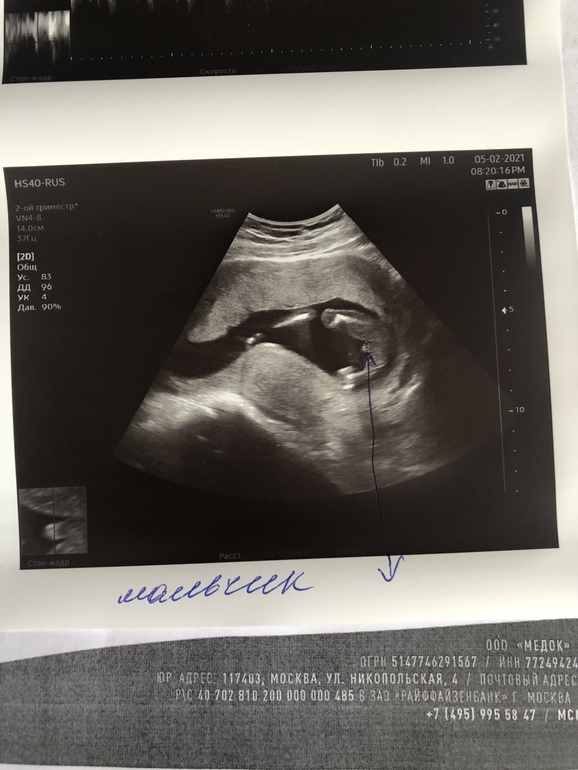

Узи в 16+6. И фото пола специально для папочки

Результаты: УЗИ, КТГ, доплера, скринингаПапа наш сразу говорил, что будет парень . Но Нипту верил не до конца. Требовал по старинке: фото писюна . Вот, получил. Даже в увеличенном виде 😁